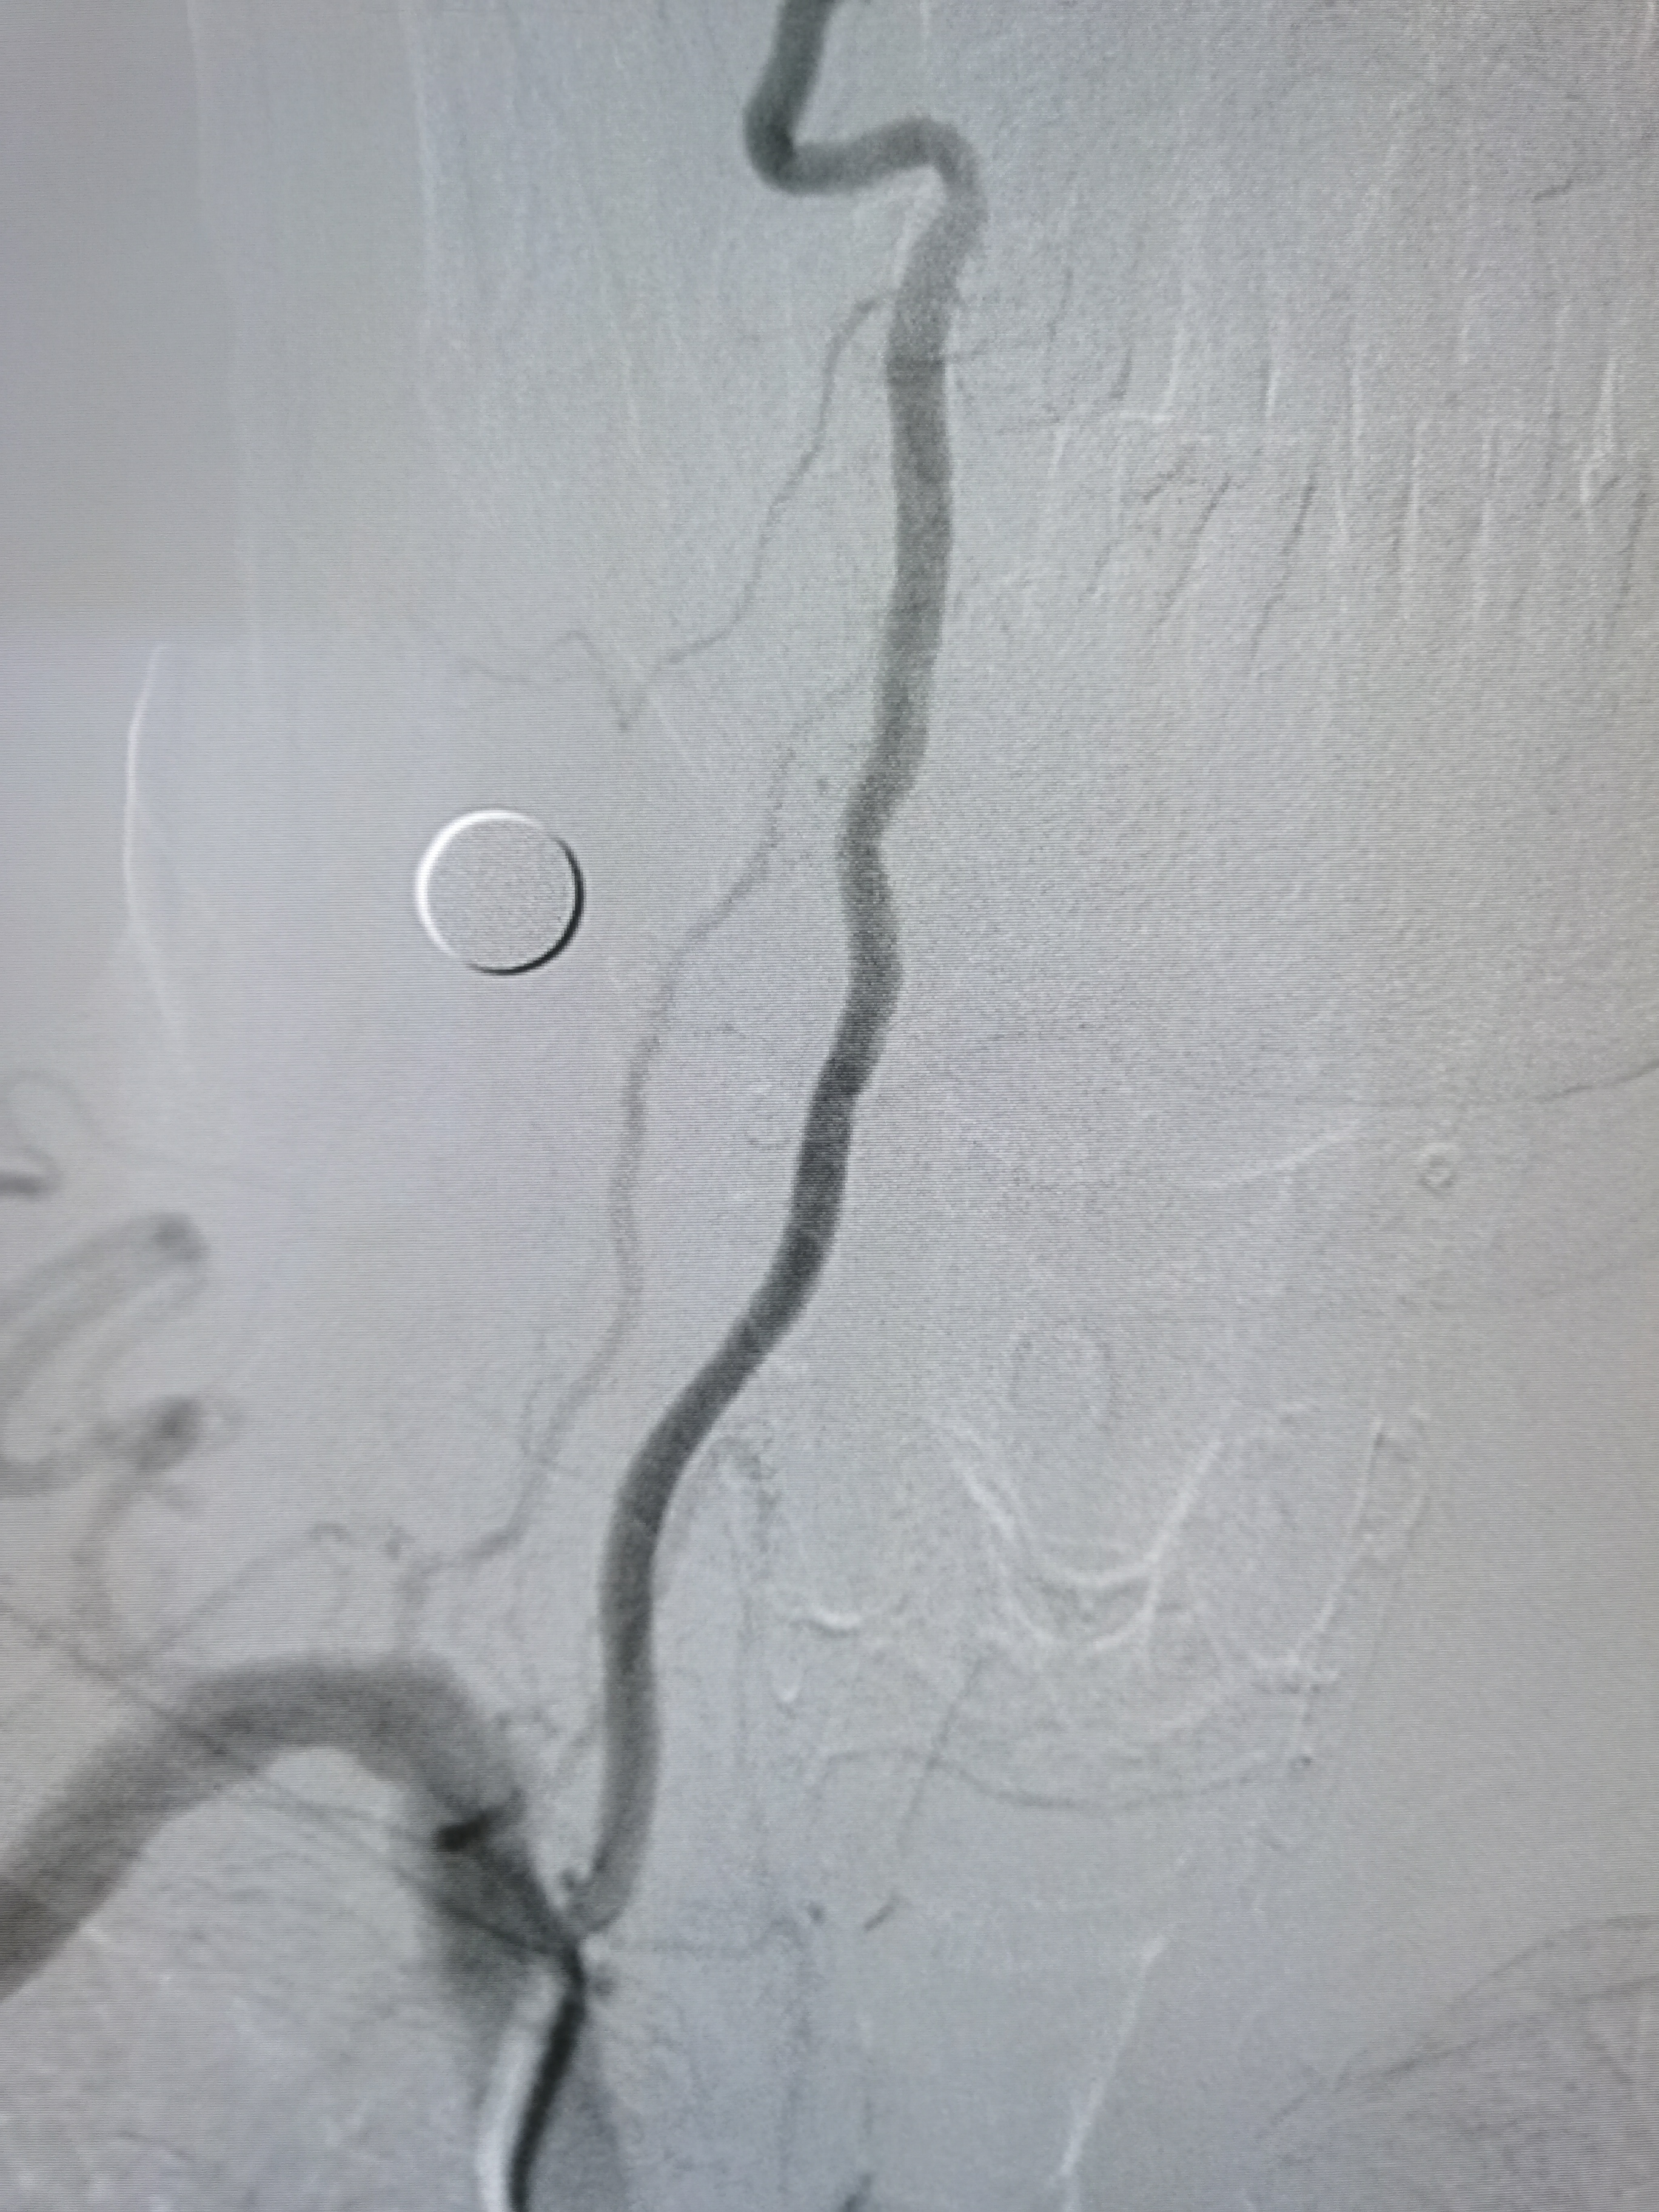

右侧颈内动脉起始部重度狭窄。